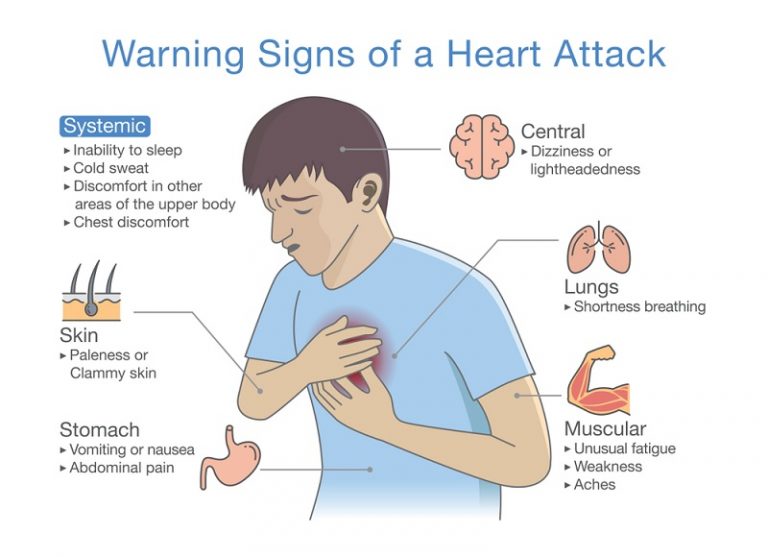

It Is Common Knowledge That The Symptoms Of Heart Attack Can Be

Heart Attack 101

Heart Attack Signs And Symptoms